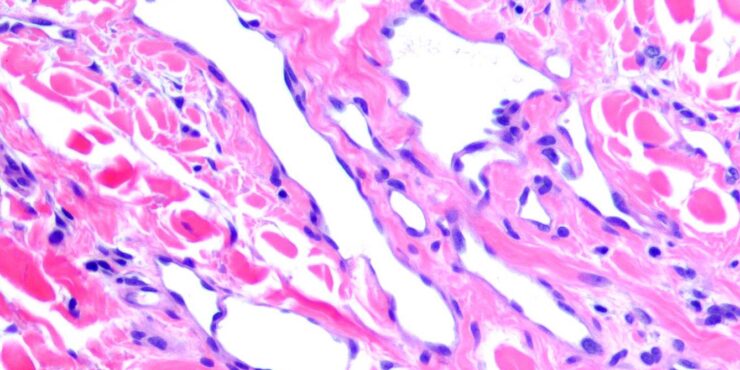

Acquired progressive lymphangioma =الورم الوعائي اللمفاوي المترقي المكتسب